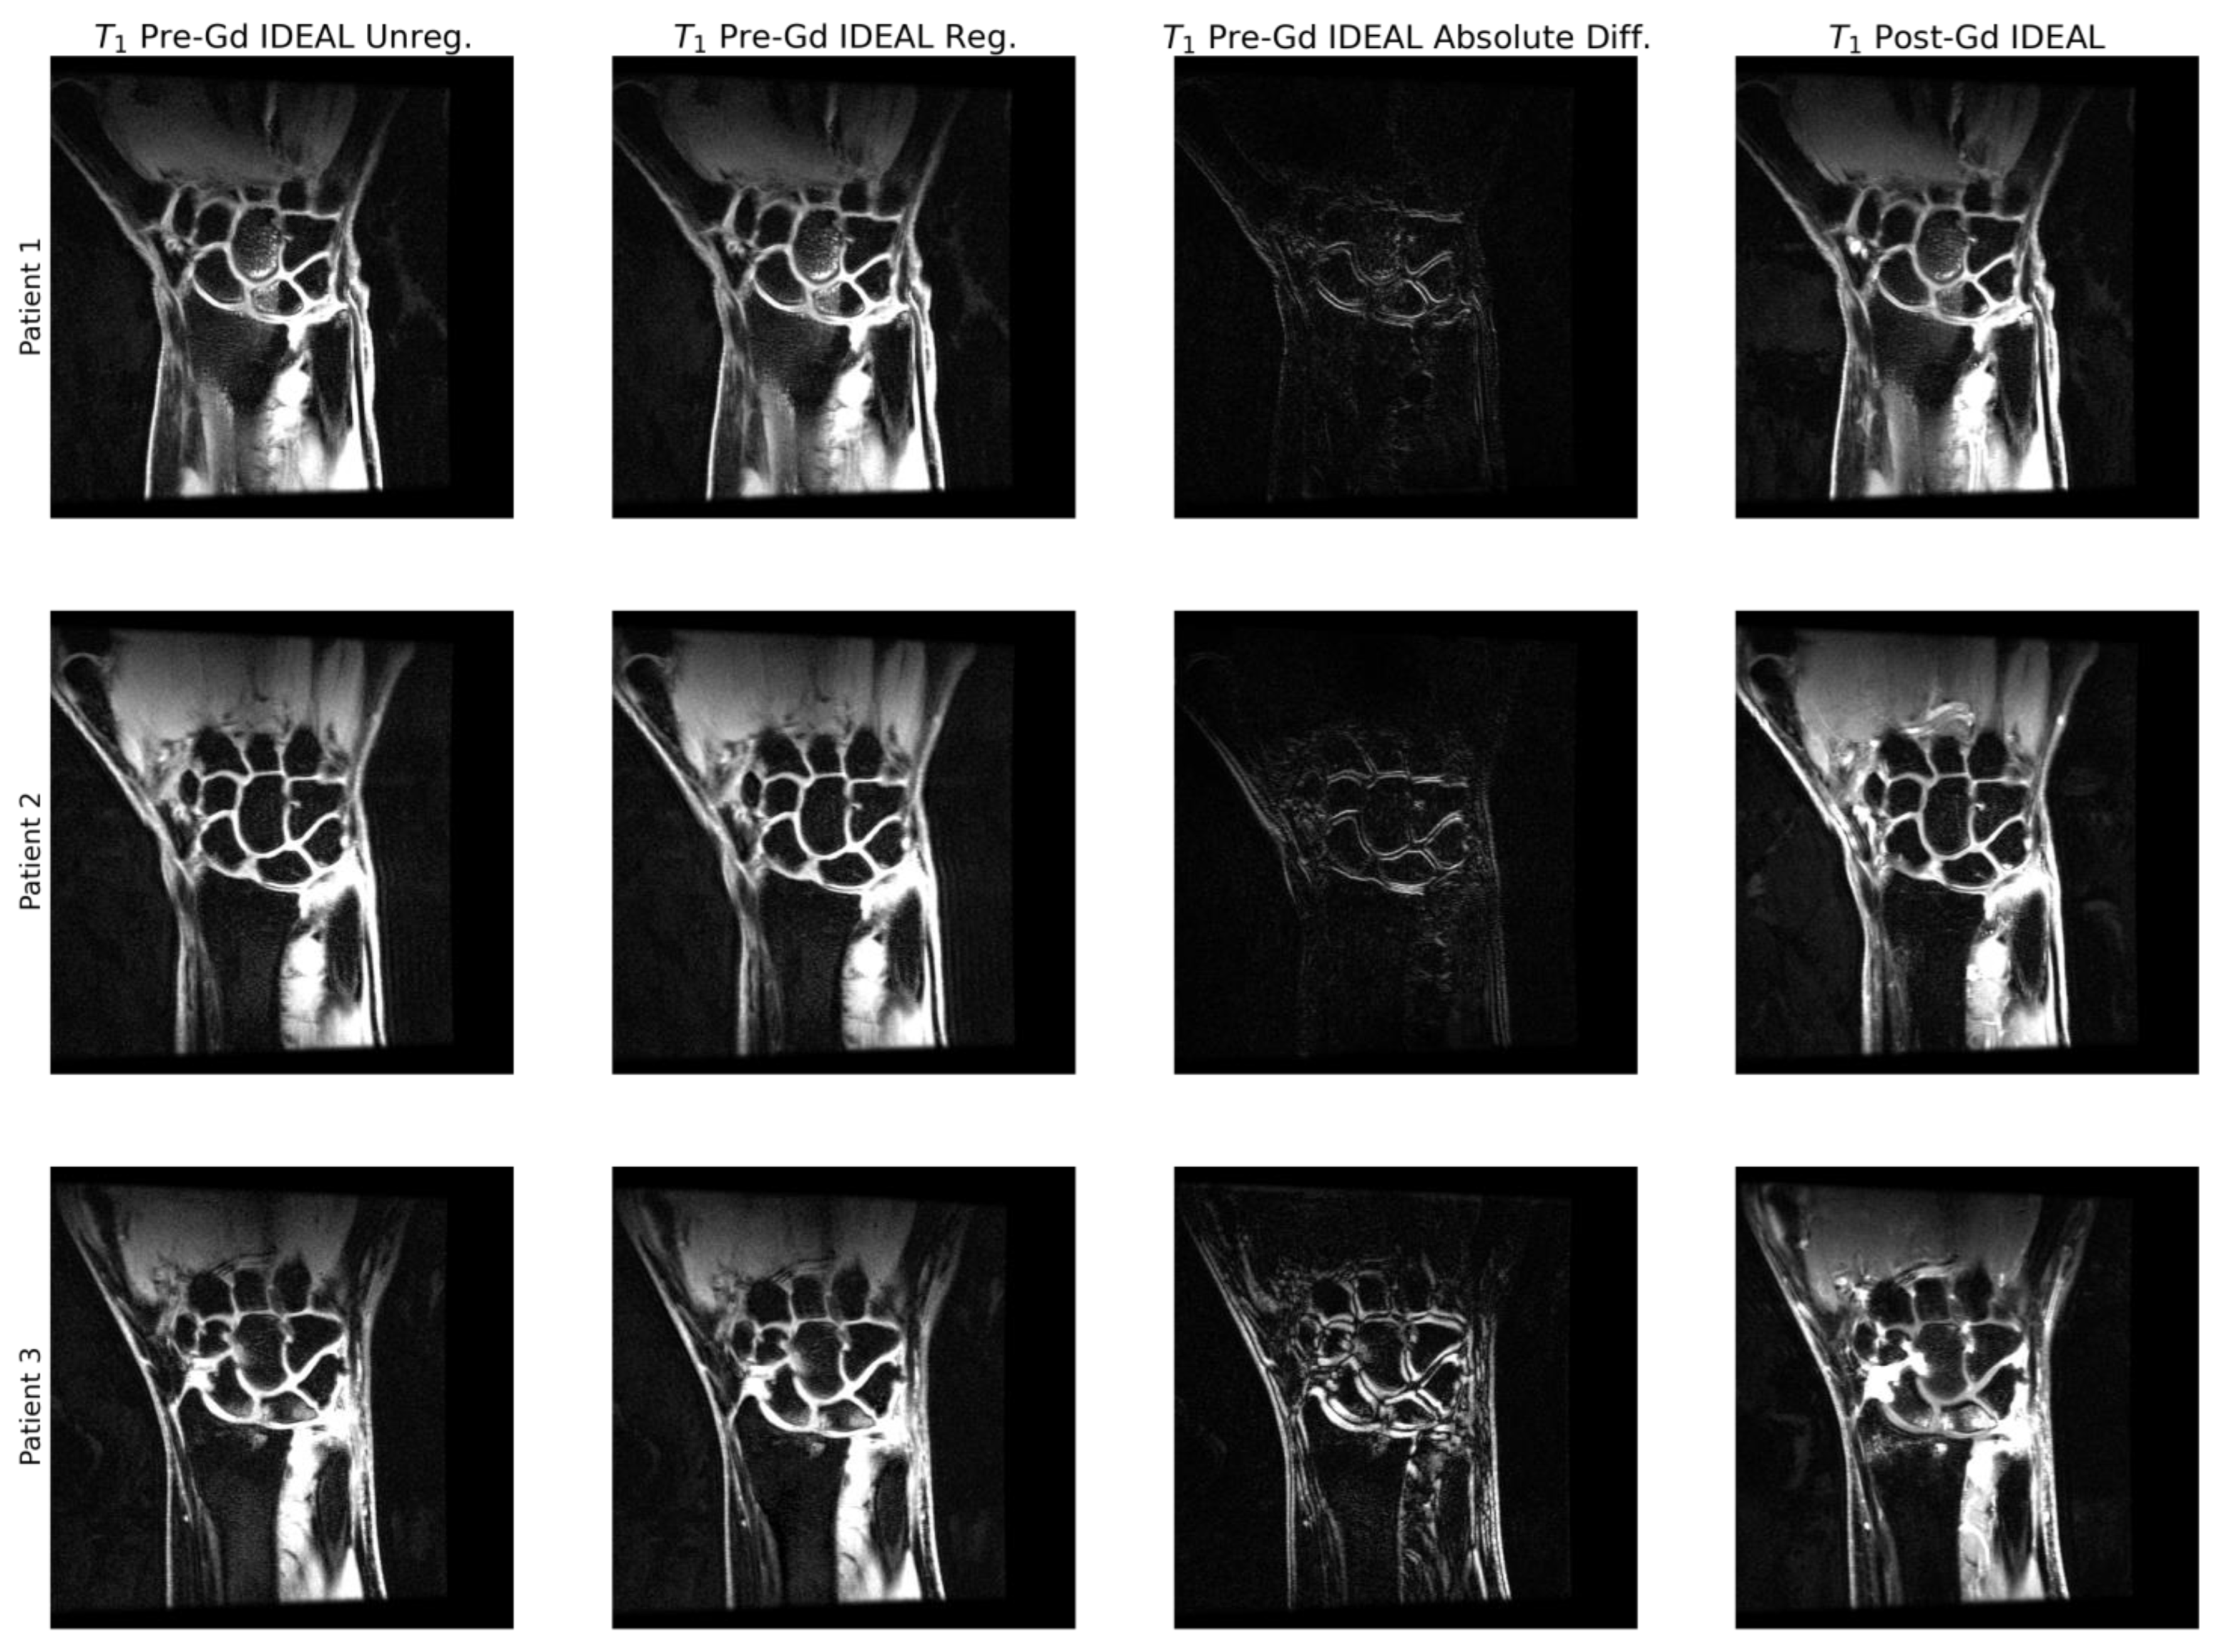

2.4. Image Preprocessing

3.2. Utility of Deconvolution Operators in Baseline UNet and PatchGAN Generator Decoders